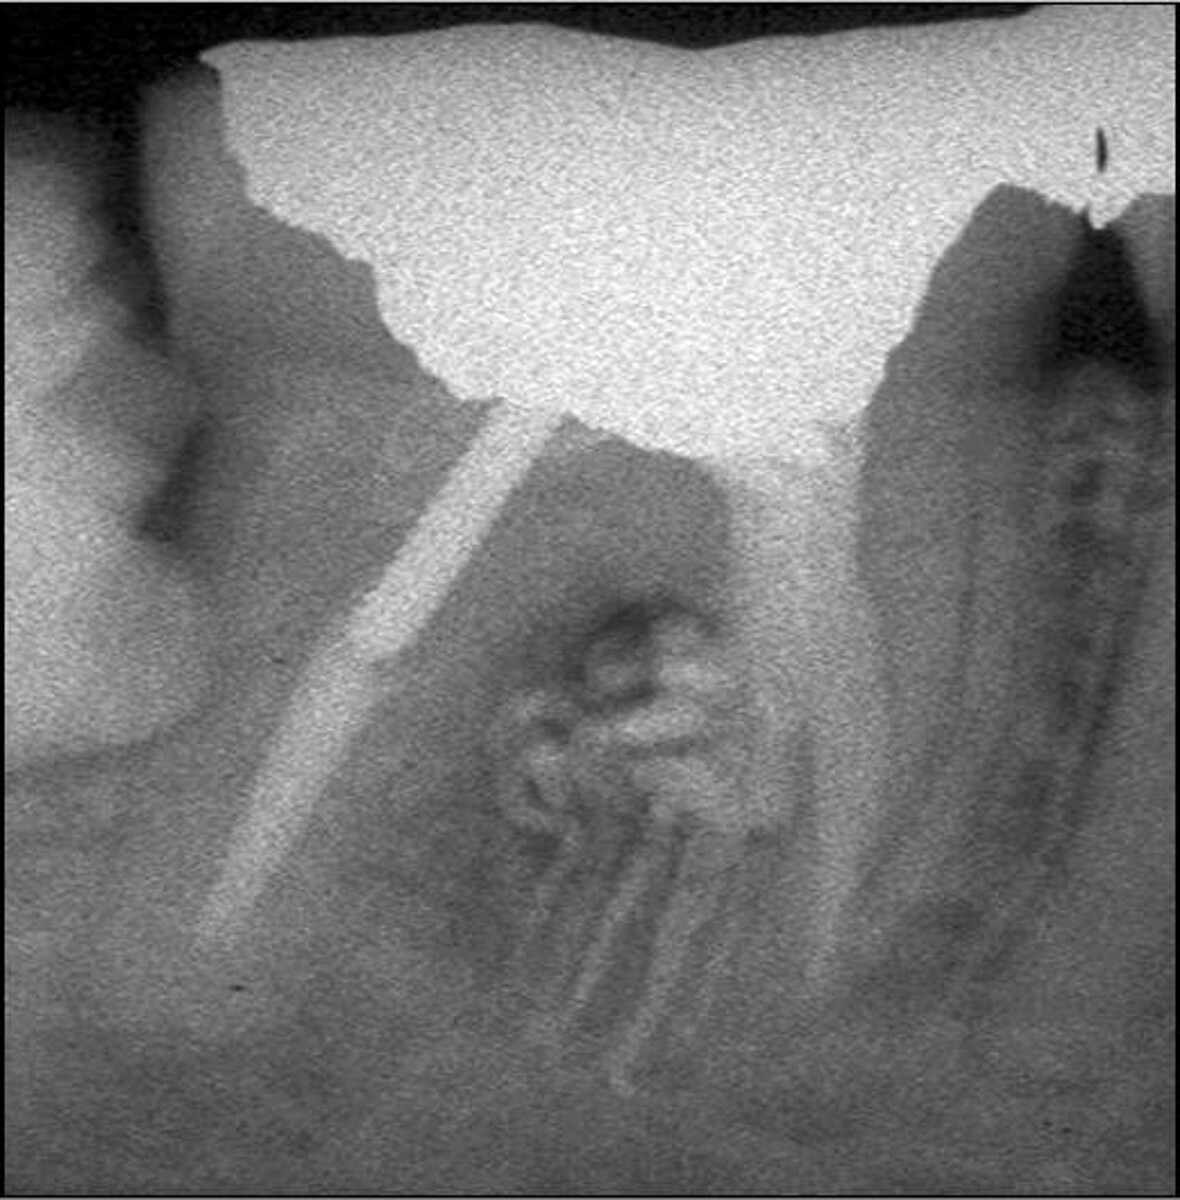

(PDF) Mandibular First Premolars With Bifurcated Root and Two canals Bifurcated Root  A bifurcation is a juncture of two roots at the base of a tooth, which can be affected by bone loss and periodontal disease. Find out the causes, symptoms, diagnosis and prognosis of furcation involvement of a dental infection. Mandibular first premolars may also exhibit a bifurcated root, one buccal, and one lingual (fig. Learn what bifurcation and trifurcation are. Bifurcated Root.